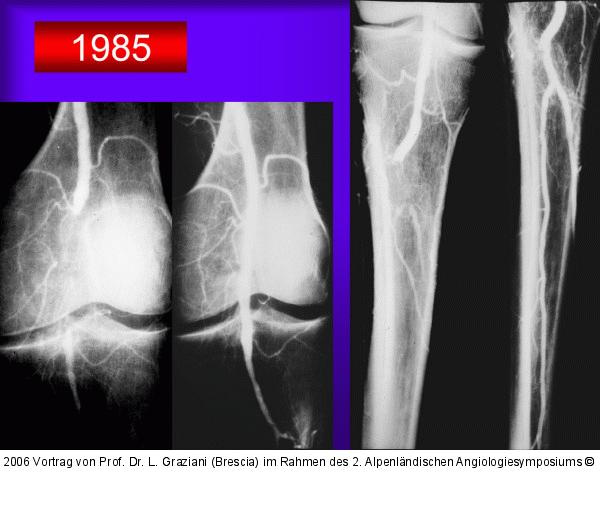

Vortrag von Prof. Dr. L. Graziani (Brescia) im Rahmen des 2. Alpenländischen Angiologiesymposiums

PTA of the foot arteries in diabetics: Extremities Extreme Angioplasty

Abbildung 34: PTA